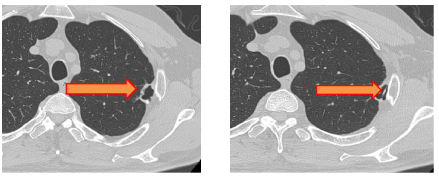

接诊后,崔健带领胸外科医疗团队为其进行了系统检查与全面评估。影像学检查发现患者左肺上叶存在异常阴影(术前影像图1、2)。团队结合临床经验初步判断并非普通肺部病变。经过与患者及家属充分沟通并完善术前准备,团队决定为王先生实施手术探查与治疗。

图1(箭头处为肺部阴影) 图2(箭头处为肺部阴影内异常密度影)